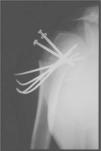

For 3- and 4-part fractures, we used the technique described by Resch et al.10: manipulation and indirect reduction of the fragments through small cutaneous portals using spatulas and hooks (Fig. 2). Once reduction was achieved, the cephalic fragment was stabilized using Kirschner wires direct from diaphysis to head or the Kapandji technique, and the tubercles were stabilized using threaded Kirschner wires or cannulated screws (Fig. 3).

Two-part fractures of the surgical neck were stabilized with Kirschner wires direct from diaphysis to humeral head in 3 instances (19%) and using the Kapandji technique, entering via the deltoid V, in 13 instances (81%). Of the greater tubercle fractures, 3 were stabilized with Kirschner wires (60%) and 2 with cannulated screws (40%).

For the 3- and 4-part fractures, the Kapandji method with threaded pins in the greater tubercle was used in 40 cases (57%) and percutaneous Kirschner wires alone in 18 cases (26%). In 6 cases (9%), percutaneous Kirschner wires with cannulated screws in the greater tubercle were used and, in 5 cases (7%), only the Kapandji method was used.